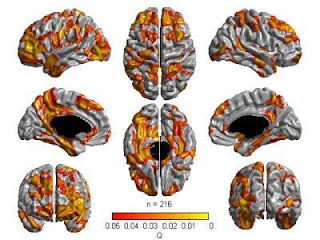

Areas in the brain where there is an association between general cognitive ability and cortical thickness. (Credit: Montreal Neurological Institute)

Cortical thickness may in part reflect the amount of complex connections between nerve cells. In other words, thicker cortices are likely to have more complex connections with consequences on cognitive ability. A positive link between cortical thickness and cognitive ability was detected in many areas of the frontal, parietal, temporal and occipital lobes. The regions with the greatest relationship were the 'multi-modal association' areas, where information converges from various regions of the brain for processing.

"A principal finding of this study is that it supports a distributed model of intelligence where multiple areas of the brain are involved with cognitive ability difference instead of the view that there is just one centre or structure important for intelligence differences in the brain," says Dr. Sherif Karama, psychiatrist at the MNI and co-investigator in the study. "Previous studies have shown a link between intelligence differences and individual brain structure or function. This is the first time that a correlation between a general cognitive ability factor and essentially most, if not all, cortical association areas is demonstrated in the same study."